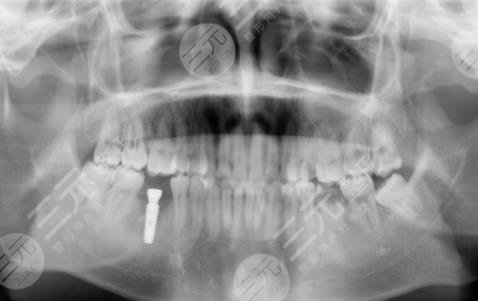

醫(yī)生看了我的牙齒情況之后,為我判斷了幾顆比較需要進行種植牙的地方進行了拔除。大概在拔完牙,一星期后我進行了種植牙,剛種上的時候還是覺得挺不舒服的,但是隨著時間的推移,我逐漸適應了自己的種植牙,并且種植的牙齒比之前更加潔白,它不單單解決了我的口腔問題,還讓我整個人的氣質都上升了不少呢。